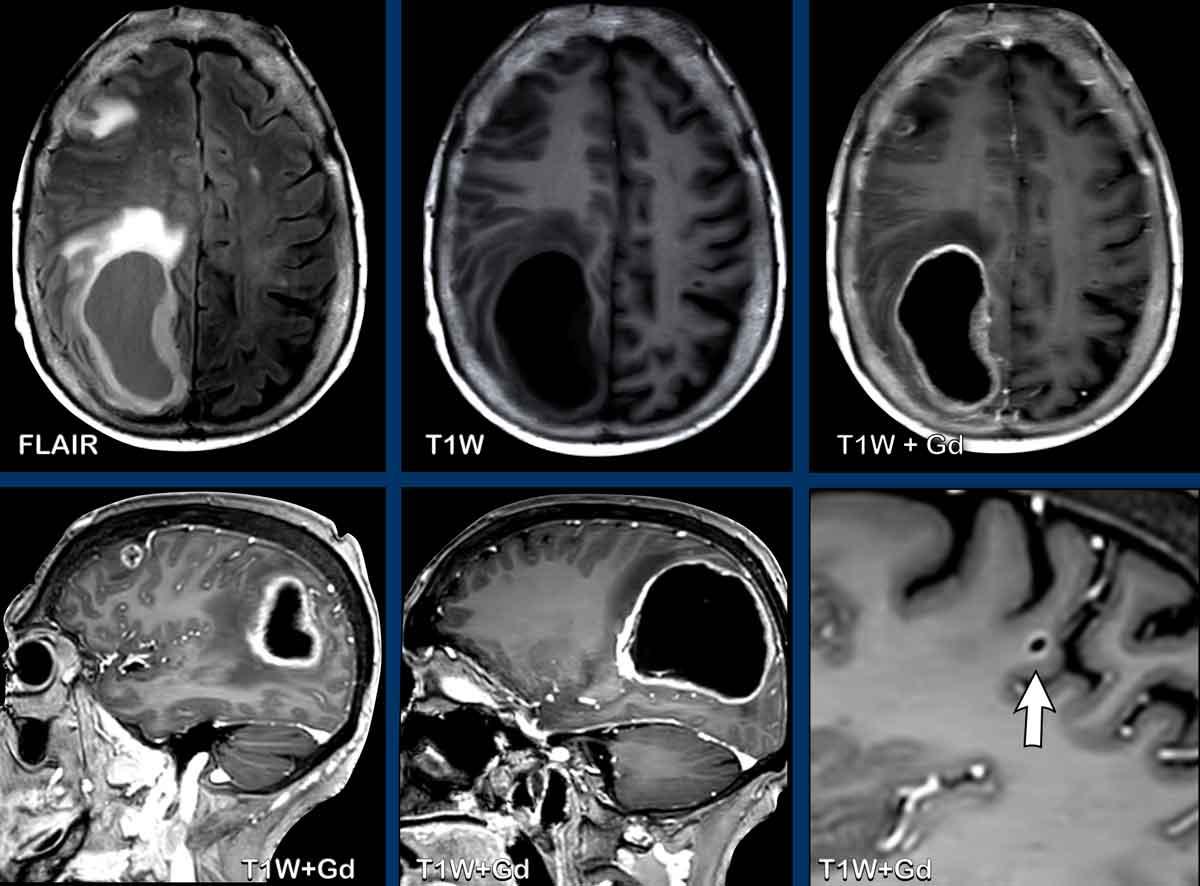

Bệnh nhân này có tiền sử ung thư phổi và nhập viện với các triệu chứng đau đầu và chậm chạp về tâm thần.

Hãy quan sát các hình ảnh trước rồi tiếp tục đọc.

Câu hỏi:

- Các dấu hiệu hình ảnh là gì?

- Chẩn đoán có khả năng nhất là gì?

Hình ảnh

Ghi nhận nhiều tổn thương ngấm thuốc dạng vòng viền liên thông nhau kèm phù não xung quanh ở bán cầu phải.

Vỏ bao tương đối mỏng và đều với hạn chế khuếch tán ở trung tâm.

Có sự lan rộng đến não thất bên phải kèm ngấm thuốc của lớp lót não thất (mũi tên).

Lưu ý thêm hạn chế khuếch tán tại tam giác não thất bên trái.

Nhiều người cho rằng đây là bệnh di căn do tiền sử bệnh, nhưng các dấu hiệu hình ảnh điển hình hơn cho áp xe não kèm viêm não thất, và đây chính là chẩn đoán cuối cùng được xác nhận.